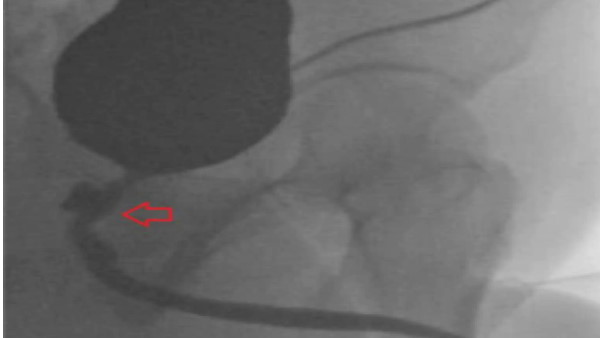

जब उस व्यक्ति पर दर्द सहन नहीं हुआ तो वह डॉक्टर के पास पहुंचा। डॉक्टर्स ने जांच में पाया कि उसके प्राइवेट पार्ट्स के साथ एक मेडिकल गलती के कारण ऐसी छेड़छाड़ हुई थी। मेडिकल जर्नल क्यूरियस में प्रकाशित एक पेपर के अनुसार, परीक्षणों से पता चला कि उन्हें मूत्र मार्ग में संक्रमण के साथ-साथ उनकी मलाशय की दीवार में भी समस्या थी। सीटी स्कैन से पता चला कि उसके पेट के अंदर 'गैस से भरी संरचना' थी, आगे के परीक्षणों से मूत्रमार्ग और मलाशय के बीच एक फिस्टुला मिला।

इसी फेस्टुला के चलते जिसके माध्यम से विभिन्न तरल पदार्थ और ठोस पदार्थ गुजर रहे थे। दो साल पहले ये शख्स ड्रग्स के ओवरडोज के कारण तीन हफ्ते तक कोमा में रहा था। उस दौरान अस्पताल में शख्स की बॉडी से गंदगी पास करवाने के लिए फॉले कैथिटर लगाया गया था। इसके जरिये कोमा में गए मरीज की बॉडी से यूरिन और पॉटी को निकाला जाता है। इस प्रोसेस के दौरान शख्स के अंदर का पार्ट डैमेज हो गया।

अस्पताल में कोमा के दौरान फॉले कैथिटर डालते समय उसके शरीर में एक सुरंग बन गई। जो प्रोस्टेट और मलाशय को जोड़ रही थी। इसके चलते शख्स के टेस्टिकल्स सूज गए थे। इतना ही नहीं उसकी बॉडी के अंदर गैस बनने की वजह से यूरिन और सीमन उसके रेक्टम में जमा होने लगा था। इस पूरी गड़बड़ी की वजह से शख्स की बॉडी में इन्फेक्शन हो गया था।